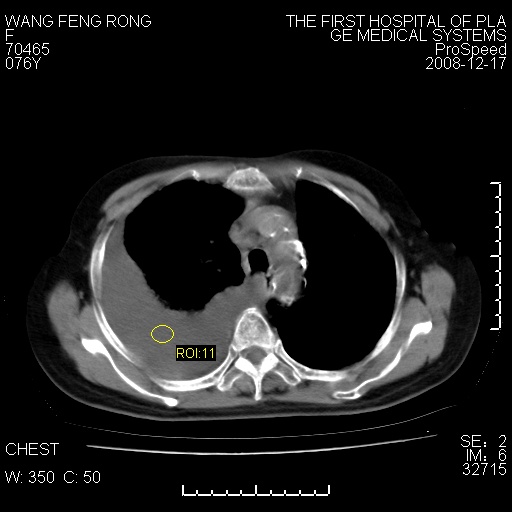

标题: CT17742:咳嗽,消瘦一月,有结果

右肺大部实变,其内可见支气管影,但分支减少,宽窄不均,走行僵直,同侧胸腔大量积液;纵隔内见多发淋巴结影,但淋巴结大部有钙化;主动脉壁钙化;临床上病人咳嗽、消瘦。所以我考虑:1、结核(依据:右下肺实变,纵隔内淋巴结符合结核表现,同侧并发胸膜炎表现);2、支气管肺泡癌(依据:实变的肺组织内支气管分支减少,宽窄不均,走行僵直,没有把它放在第一诊断是因为没有看到明显肿大的淋巴结);3、动脉硬化(主动脉壁钙化就支持这个诊断)。

病理结果,肺泡癌